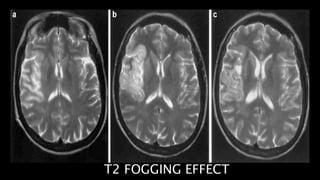

Subacute infarct shows

“T2 FOGGING EFFECT” in which

of lipid

laden macrophages

decrease in edema

T2 FOGGING EFFECT

• #84  These are the axial T2WI taken at sequential intervals of a patient with R MCA territory infarct showing T2 fogging phenomenon with decrease in the the signal intensity over the period of time almost reaching to isointensity in 3rd image